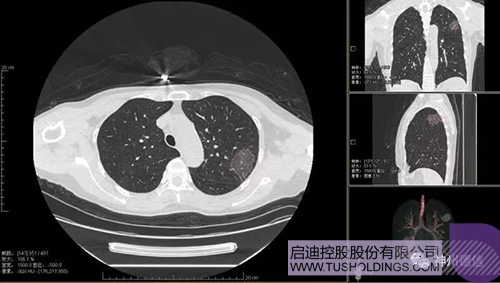

神州德信新冠肺炎检测及智能量化分析系统

乐鱼app官网登录入口-乐鱼(中国)

战略投资企业神州德信作为国内领先的肺部影像人工智能企业,针对新型冠状病毒肺炎开发了智能检测及量化分析系统,并在陕西、重庆等地定点医院投入使用。该系统在疑似病例大规模快速筛查及精准诊断方面发挥了重要作用,特别是其具有的肺炎患者临床影像跟踪量化随访功能,为快速有效阻断疫情扩散提供了有力武器。